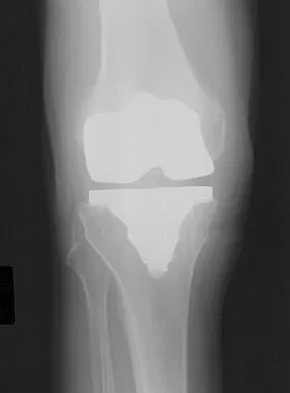

Figures 12a and 12b show the radiographs of a 50-year-old patient who reports acute knee pain after sustaining a twisting injury while playing tennis. Examination is unremarkable. The next most appropriate step in management should consist of

The radiographs show localized diffuse cortical thickening that is characteristic of melorheostosis. The condition may be monostotic or it may involve many bones in one extremity (monomelic) in the distribution of a sclerotome. Bone scans will show increased uptake at the site or sites of skeletal involvement. Long tubular bones are most commonly involved. Melorheostosis is usually asymptomatic and requires no treatment. On rare occasions, there may be associated soft-tissue contractures. Dorfman H, Czerniak B: Bone Tumors. St Louis, MO, Mosby Inc, 1998, pp 1105-1107. Campbell CJ, Papademetriou T, Bonfiglio M: Melorheostosis: A report of the clinical, roentgenographic, and pathological findings in fourteen cases. J Bone Joint Surg Am 1968;50:1281-1304.